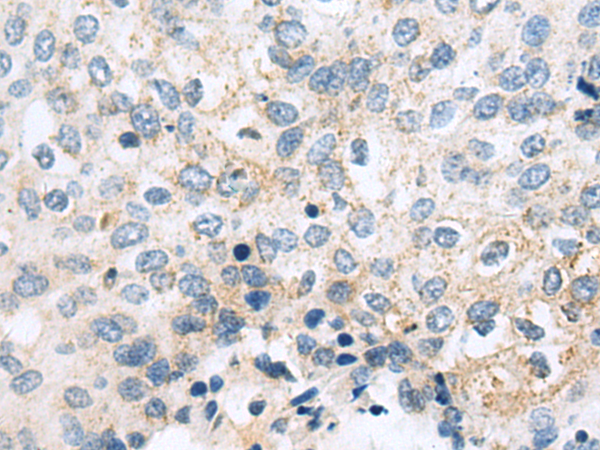

分类: 科研抗体货号: P06944别名: FN; CIG; FNZ; MSF; ED-B; FINC; GFND; LETS; GFND2应用: IHC反应种属: Human, Mouse, Rat